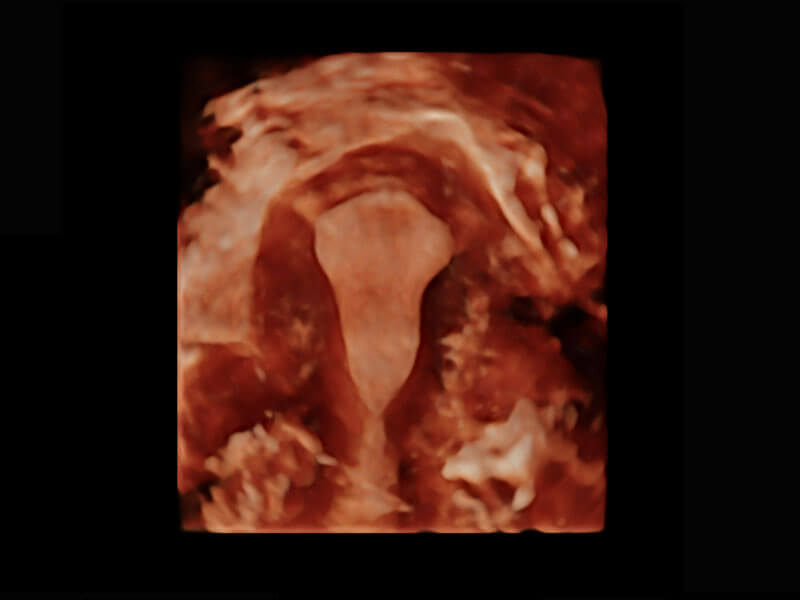

P60優(yōu)異的圖像質(zhì)量搭載專科探頭,在婦科基礎(chǔ)疾病的診斷、卵泡生長(zhǎng)的監(jiān)測(cè)、輸卵管通暢情況的判別等方面為您提供生殖應(yīng)用方案。

腔內(nèi)三維-宮內(nèi)節(jié)育器

腔內(nèi)三維-光影成像